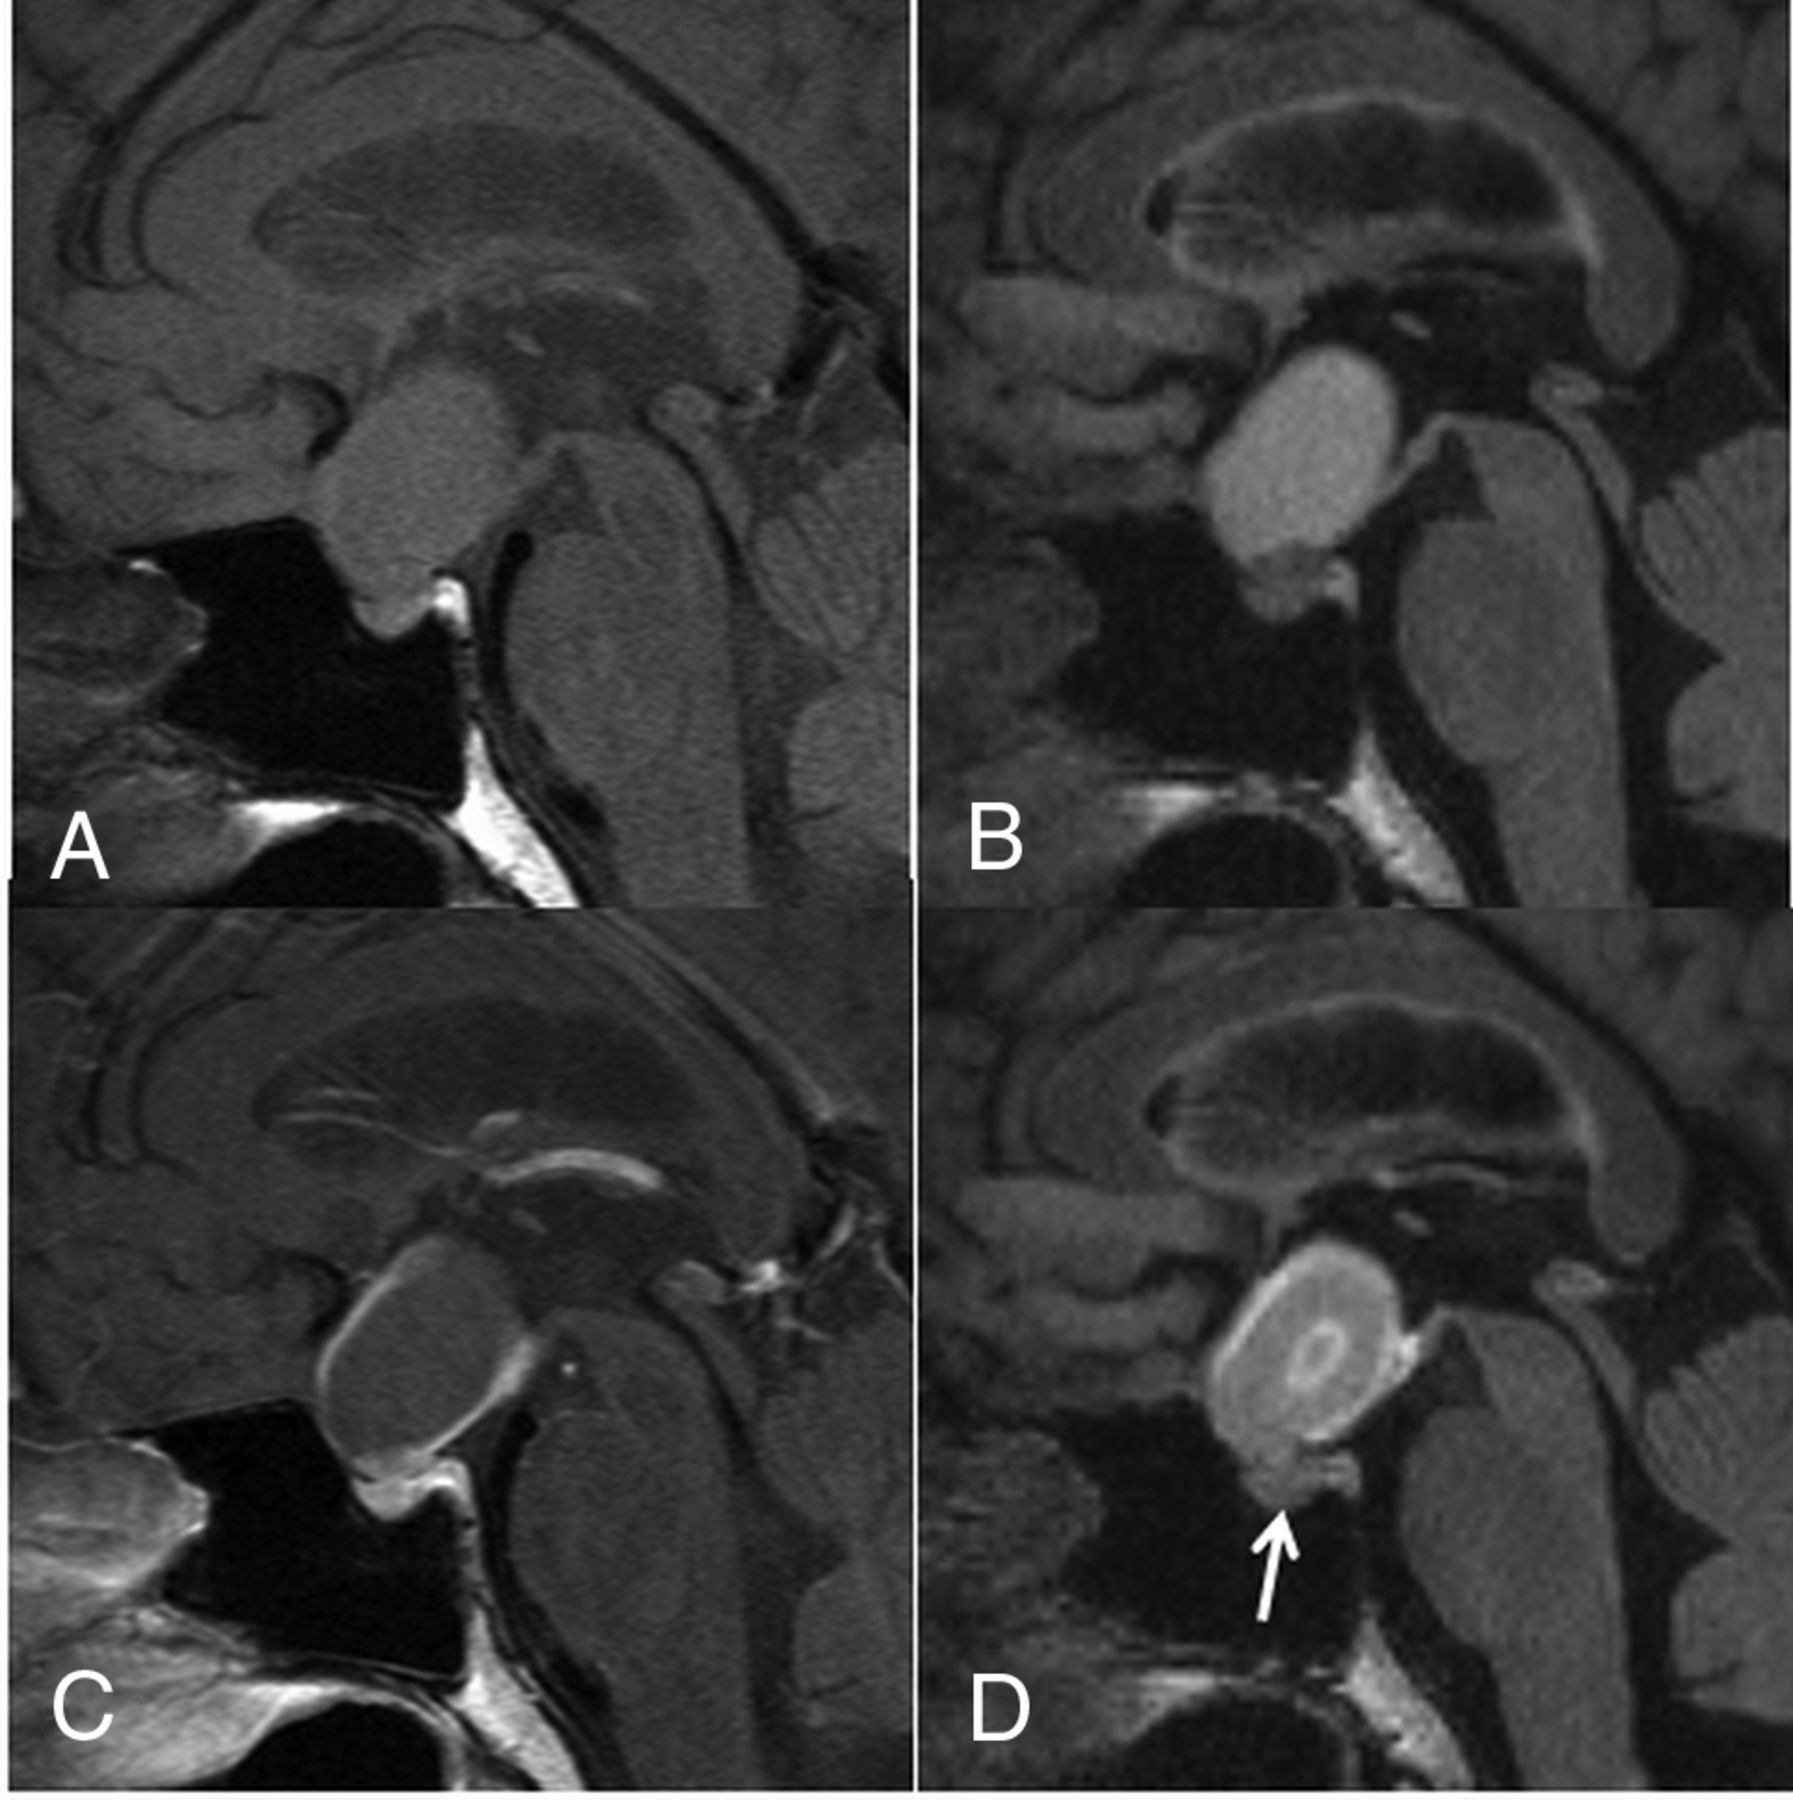

A 44-year-old woman with a CCP. A comparison of pre- (A) and postcontrast T1WI (C) shows that the cyst wall is enhanced on the postcontrast image (grade 2). A comparison of pre- (B) and postcontrast 3D T2-FLAIR images (D) reveals enhancement of the cyst wall (grade 2) and the lesion center on the postcontrast image (D). Different from the postcontrast T1WI (C), the pituitary gland is not intensely enhanced on the postcontrast 3D T2-FLAIR image (arrow in D). The observer judged this lesion as probably an RCC (scale 2) at the conventional MR interpretation, whereas the confidence level was changed to probably a CCP (scale 4) by the addition of 3D T2-FLAIR interpretation.

A retrospective review revealed the reasons for incorrect interpretation for 2 of 17 (11.8%) conventional MR readings (first interpretation session). In one patient with an RCC, the lesion determination on conventional MR interpretation was a false-positive result due to the presence of a solid component on CE T1WI (Fig 4), which was correctly interpreted as normal anterior pituitary gland by adding the 3D T2-FLAIR images (second interpretation session). In 1 patient with a CCP, the false-negative result of a conventional MR interpretation was attributed to a homogeneously enhanced cystic wall (Fig 5).